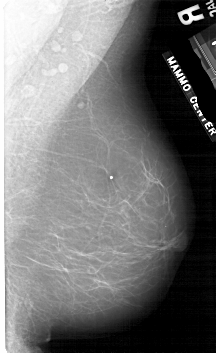

A_1754_1.LEFT_CC

LEFT_CC LINES 5491 PIXELS_PER_LINE 3556 BITS_PER_PIXEL 12 RESOLUTION 43.5 OVERLAY

FILE: A_1754_1.LEFT_CC.OVERLAY

TOTAL_ABNORMALITIES 1

ABNORMALITY 1

LESION_TYPE MASS SHAPE ROUND MARGINS CIRCUMSCRIBED

ASSESSMENT 3

SUBTLETY 4

PATHOLOGY BENIGN

TOTAL_OUTLINES 1

BOUNDARY